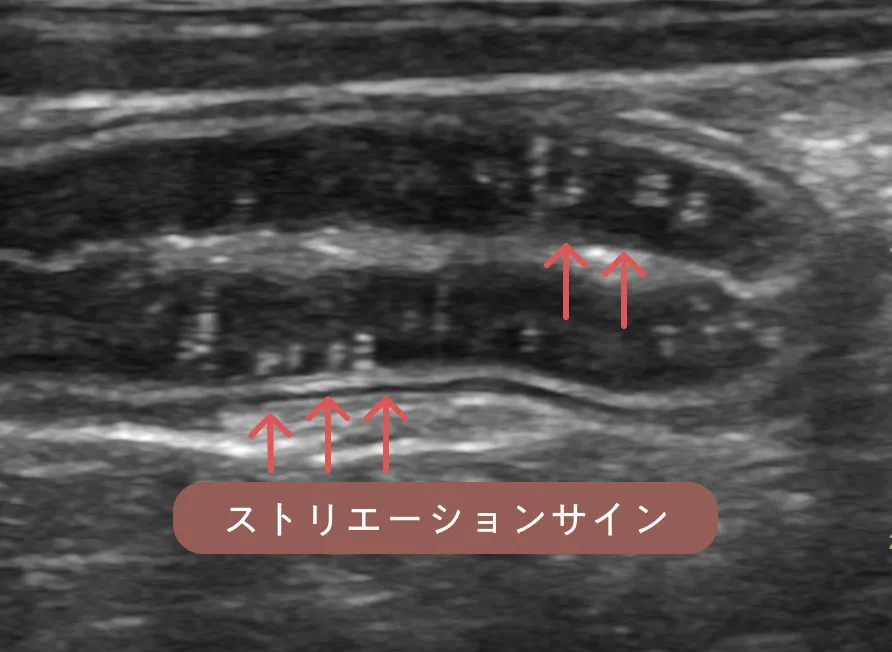

身体検査では軽度の削痩を認めました。血液検査では低アルブミン血症(2.1 g/dl)を認めました。エコー検査では小腸の広範囲でリンパ管拡張を示す白い縦縞のストリエーションサイン(正常な腸には見られない、エコーで映る縞模様 _ 赤矢印)と微量腹水(青矢印)が見られました。

ストリエーションサインは特に空腸で重度にみられ、隣に描出した十二指腸の粘膜層(黒く分厚い層)と比較してかなり白く見えます(黄矢印)。各検査から可能性のある病気を除外し、蛋白漏出性腸症を強く疑いました。全身状態も悪くないため、ご家族と相談し、内視鏡検査を行う前にまずは食事療法の反応性を確認します。